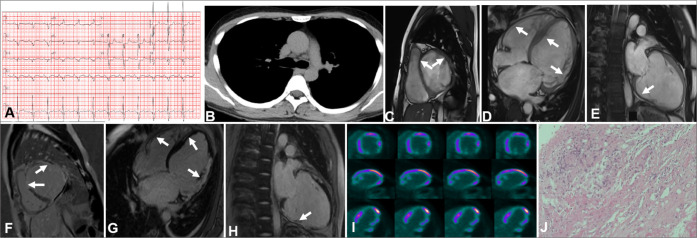

Cardiac sarcoidosis (CS) represents a rare yet potentially life-threatening condition characterized by non-specific clinical symptoms that maybe easily missed by clinicians. In this case series, the clinical presentations, various imaging modalities' characteristics, and the management of four patients, each with distinct phenotypes of CS confirmed through endomyocardial biopsy, are discussed. Advanced imaging techniques, including positron emission tomography, revealed the focal septal uptake of 18F fluorodeoxyglucose, which suggests an ongoing inflammation, whereas contrast-enhanced cardiac magnetic resonance demonstrates septal late gadolinium enhancement, which indicates replacement fibrosis. These features of multimodality imaging in CS can assist in patient diagnosis and treatment.